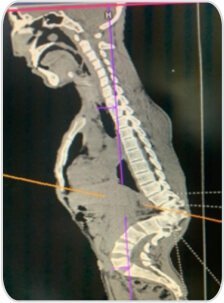

Pre-operative ct scan showing deformed spine of the patient with VRT showing unsegmented posterior hemivertebra

Intra op image after corpectomy and instrumentation Complete vertebral column resection was done in posterior approach with posterior instrumentation and deformity correction